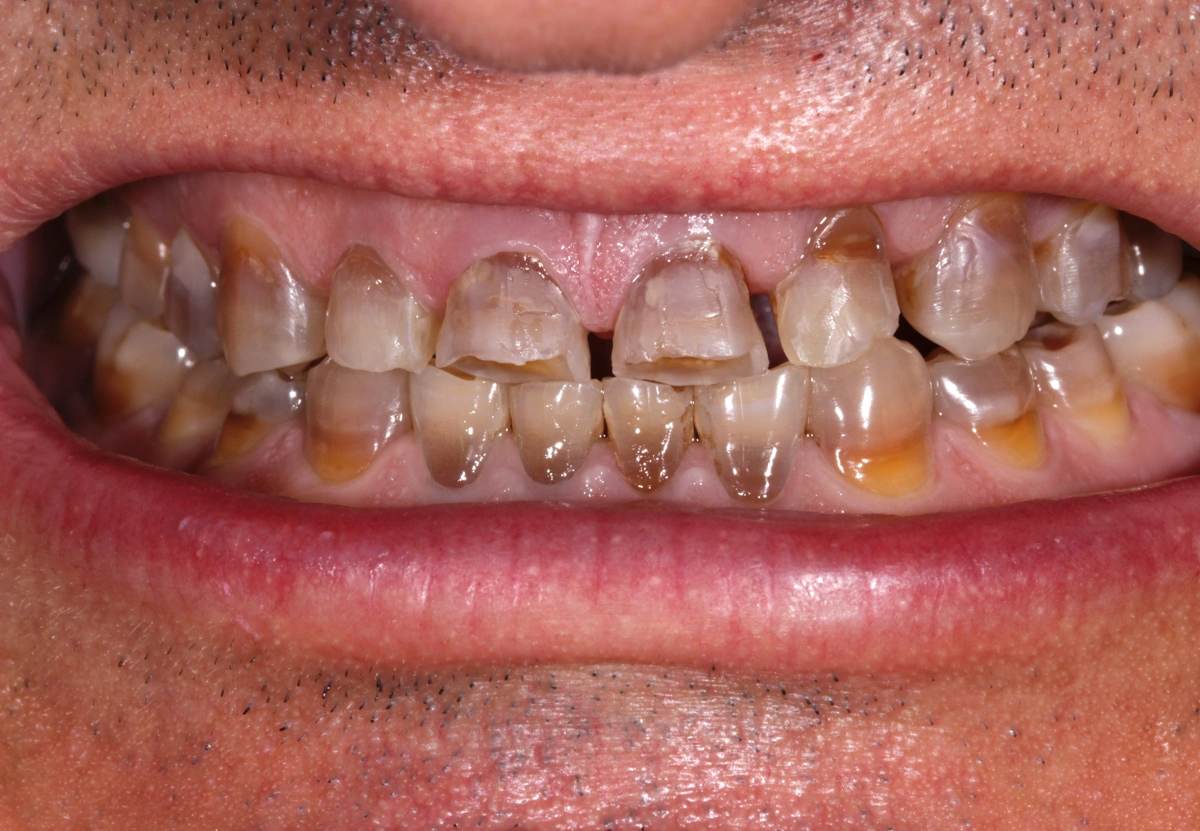

Paciente joven acude a consulta referido por el ortodoncista para tratamiento de desgaste.

La tetraciclina era un medicamento que se administraba en los años 50 que a posteriori se han podido observar los efectos secundarios que tienen en la boca: tinción dental intrínseca. Existen distintos grados y en función de su severidad. Las tinciones por tetraciclinas suponen un reto a nivel restaurador.

En este caso se trata de un paciente con desgaste dental severo y tinción por tetraciclinas grado IV.